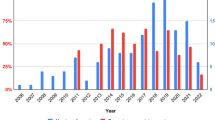

The study characteristics are shown in Table 1: Of the nine included studies, five were prospective [3, 20,21,22,23] and four were retrospective [4, 24,25,26]. Study samples varied from 9 to 76 included patients with a broad age range, and median 86% male participants (range 66–92%). Follow-up varied from 6 to 58 months. Only studies with central or central and peripheral vascular grafts were included. Few studies have linked graft localization to outcome, so further analysis was not performed. Six studies employed a low-dose, unenhanced CT, whereas three studies used full diagnostic CT with contrast enhancement. A total of 325 patients underwent FDG-PET/CT. In most studies, clinical follow-up and further imaging were used when the suspicion of graft infection was considered low [3, 4, 20,21,22,23,24,25,26,27]. The FDG-PET/CT scans were assessed using qualitative or semi-quantitative methods, i.e., FDG uptake patterns, SUVmax, or TBR. Only SUVmax did not exhibit statistical significant signs of funnel plot asymmetry due to small-study effects across several parameters.

Qualitative assessment of uptake pattern: focal/diffuse or VGS

Five studies interpreted images to be qualitative based on uptake patterns, i.e., focal or diffuse uptake patterns of FDG, with a focal pattern implying a higher risk of VGI than a diffuse pattern [20,21,22,23, 26]. The pooled sensitivity and specificity (95% CI) were 90.6% (81.7–99.4%) and 82.8% (71.3–94.3%), respectively. Pooled PPV, NPV, and accuracy were 83.9%, 90.8%, and 87.2%, respectively (Fig. 2).

Two of these also used five-point VGS (0–4), albeit different ones [22, 26]. The pooled sensitivity and specificity (95% CI) were 86.8% (59.3–100.0%) and 69.4% (39.9%–98.9), respectively. Pooled PPV, NPV, and accuracy were 81.7%, 81.1%, and 85.5%, respectively (Fig. 2).

SUVmax and TBR

Six studies interpreted images according to SUVmax [3, 22] [4, 24,25,26]; the pooled sensitivity and specificity for SUVmax (95% CI) were 92.8% (83.2–100%) and 69.7% (52.4–86.9%), respectively; estimated mean values for PPV, NPV, and accuracy were 84.1%, 80.3%, and 85.5%, respectively (Fig. 2).

Only one study assessed TBR; Berger et al. did not specify the location of the blood pool [26]. The pooled sensitivity and specificity (95% CI) were 71.8% (54.6–84.4%) and 70.4% (51.5–84.2%), respectively. There were a pooled PPV, NPV, and accuracy of 74.2%, 67.9%, and 71.2%, respectively.